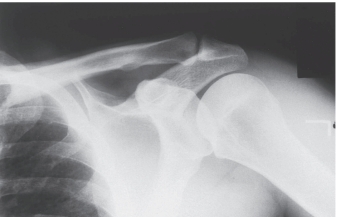

-Refer to the figure. Name the radiographic projection.

A) Anteroposterior external rotation

B) Lateral view of the scapula

C) Anteroposterior internal rotation

D) Axillary view of glenohumeral joint

Anteroposterior internal rotation

3

-Refer to the figure. You have chosen the correct answer because you recognized what region of anatomy seen in profile?

A) Greater tuberosity

B) Acromioclavicular joint

C) Lesser tuberosity

D) Coracoid process

Lesser tuberosity